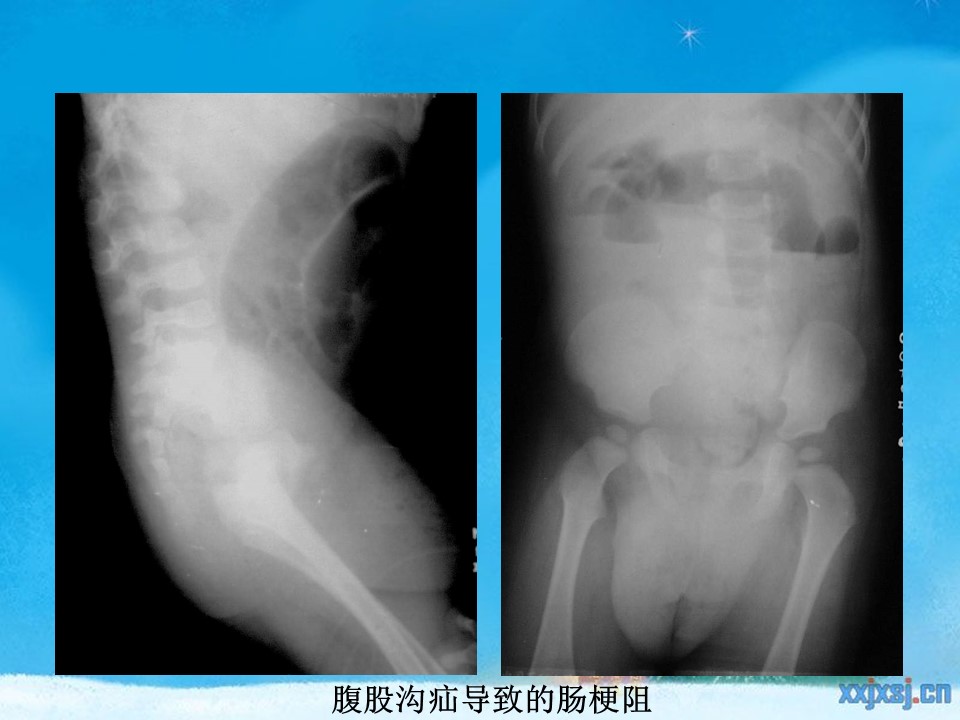

“腹部、盆腔影像诊断学PPT” 的相关文章